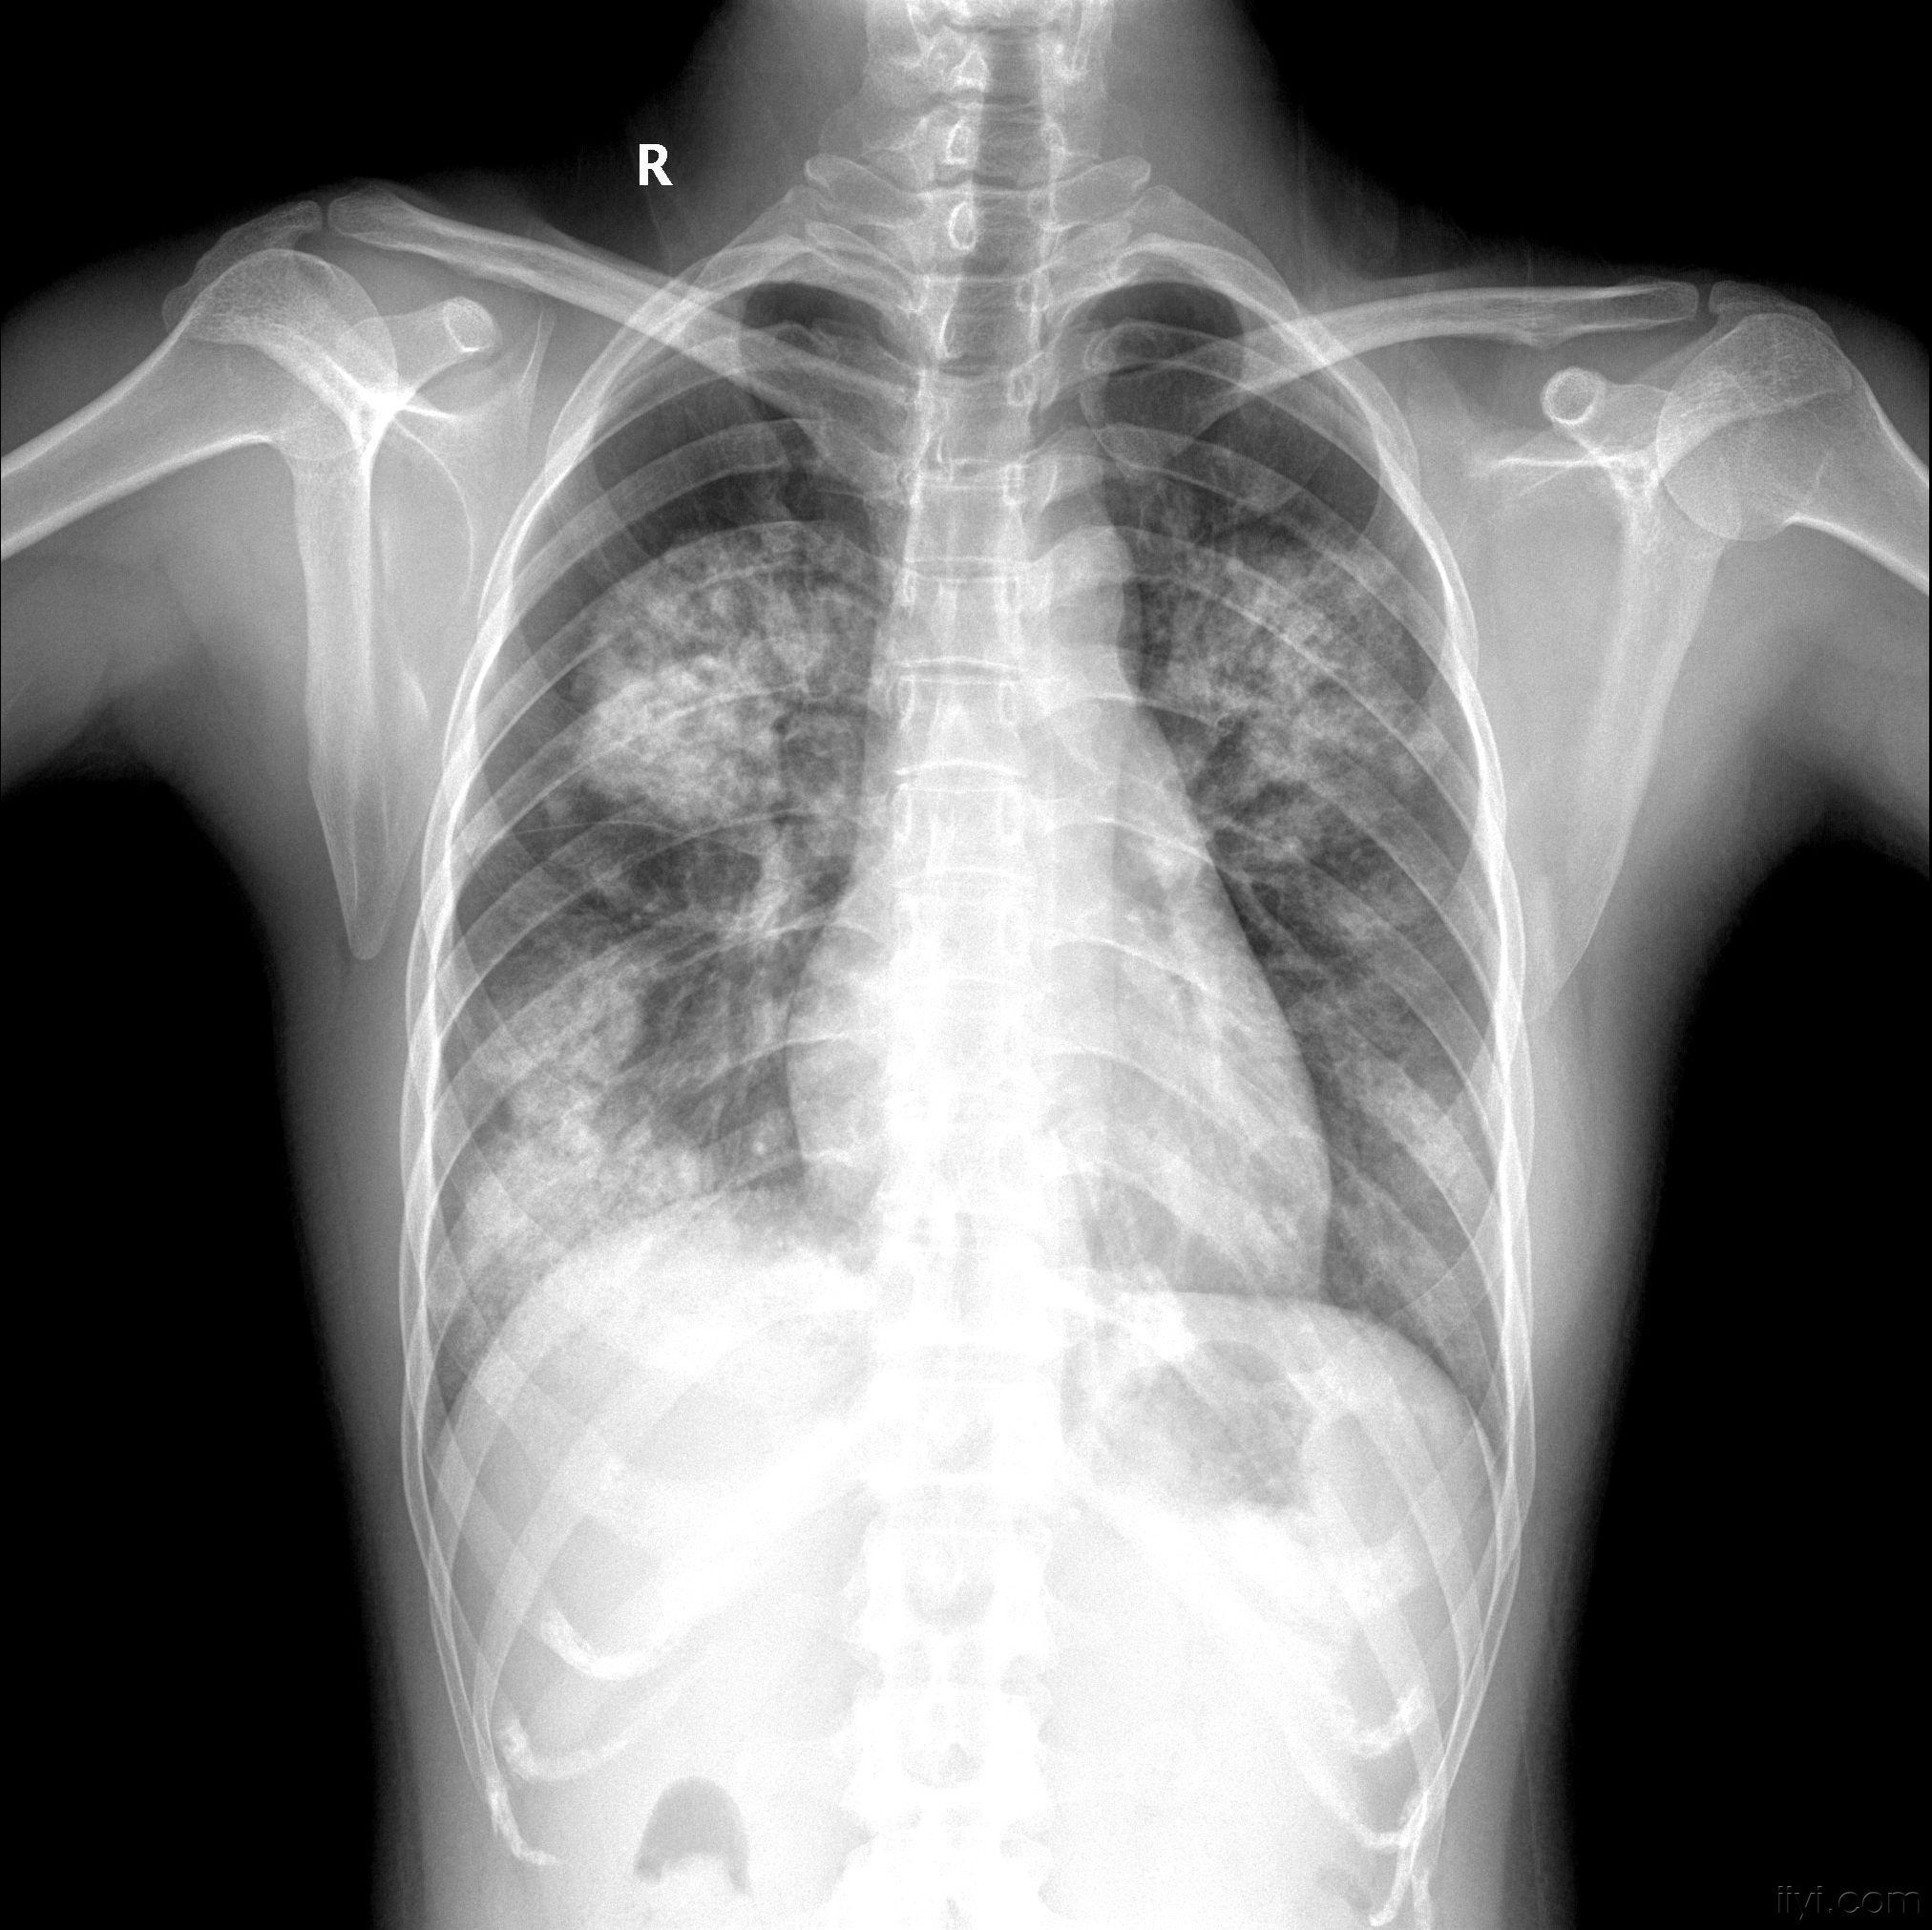

浸润性肺结核

肺渗出(浸润)性病变:浸润型肺结核.

胸部 x 线: 显示片状浸润,间质浸润,肺泡浸润, 腔,纤维化肺由于结核

肺结核 (tb): 胸部 x 光显示肺泡浸润在这两个由于结核杆菌感染的肺